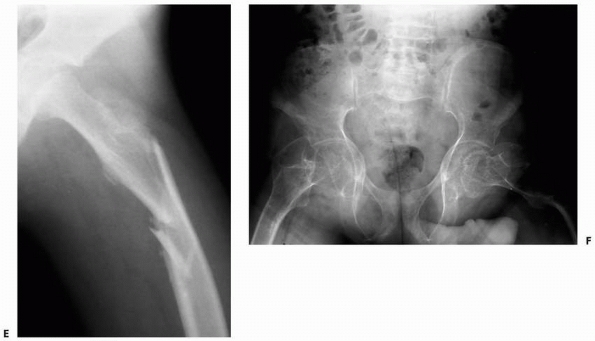

FIGURE 6-18

A 13-year-old boy presented with several months history of right arm pain and recent increase in pain following minor trauma. Anteroposterior (A) and lateral (B) radiographs show a minimally displaced midshaft humeral pathologic fracture through a poorly defined, permeative, aggressive-looking diaphyseal lesion. (C) T2-weighted axial MRI shows a huge soft tissue mass associated with the bone lesion and involvement of the neurovascular bundle. The patient was diagnosed with Ewing sarcoma, received neoadjuvant chemotherapy, and had a shoulder disarticulation (D), followed by postoperative chemotherapy. (Figures reproduced with permission from The Childrens Orthopaedic Center, Los Angeles, CA.) |